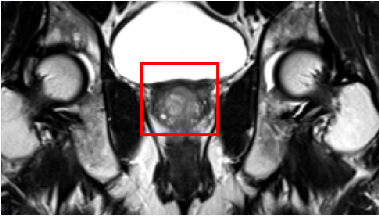

核磁共振显示前列腺恶性肿瘤(红框内)

做好充足的术前准备后126燚星主任医师郭玺副主任医师带领手术团队为患者在全麻下施行经脐单孔腹腔镜下筋膜内保留血管神经束前列腺癌根治术+膀胱颈重建术+盆腔粘连松解术手术历经约2.5小时,切下的肿瘤及受累的双侧精囊腺和输精管约7×4cm,足有鸡蛋大小